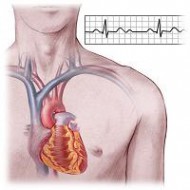

A diagnózis a szindróma MAC fő hangsúlyt kap az EKG technikák - nyugalmi EKG, napi követése. ultrahang, angiográfia lehet nevezni, hogy tisztábban lássuk a szívbetegség. Ugyanilyen fontos a hallgatózás, ha orvos is hallgathatja sajátos zajokat nyereség az első hang, az úgynevezett három tagú ritmus és így tovább. G. De hallgatózási jelek feltétlenül esnek egybe az EKG adatokat.

Mivel Adams betegség - következtében a különböző típusú vezetési zavarok, valamint a EKG-diagnosztikai kritériumok mint ilyen, nem rendelkezik, és a jelenség az EKG társított típusú ritmuszavar. által kiváltott egy adott beteg számára.

Megsértése esetén a pitvari csomópont értékelni az EKG, különösen időtartama intervalaPQ. amely tükrözi az időben a pulzus a vezetési rendszer a szinusz csomó a kamrák a szív.

Az első fokú blokád ez az intervallum nagyobb, mint 0,2 másodperc, a másodfokú intervallumot fokozatosan megnyúlt vagy magasabb, mint a normál minden szív komplexek, a QRST időszakosan csökkent, jelezve, hogy a következő impulzus csak nem érte el a kamrai szívizomban. A harmadik és legsúlyosabb blokád, a pitvarok és a kamrák magukat, száma kamrai komplexek nem felel meg a P hullám, amely impulzusok a sinus csomópont nem éri el a végpontot a vezető szálak a kamrák.